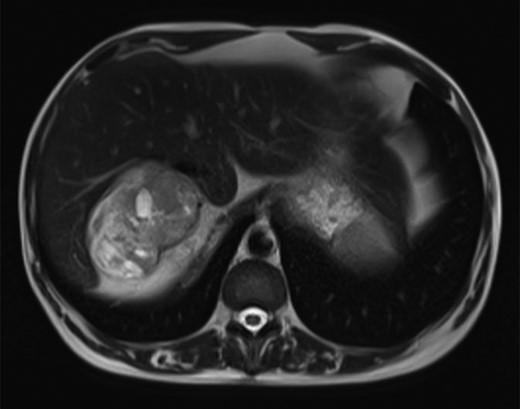

The magnetic resonance imaging (MRI) found the mass, which was measured at 85 × 60 × 160 mm, heterogeneous, with isointense and T1-weighted hyposignal (Fig. 2), isointense and T2-weighted hypersignal (Figs 3 and 4), and diffusion-weighted heterogeneous hypersignal. After injection of the contrast product, the mass did not appear to be hypervascular, and uptake was more pronounced in the late phase, indicative of a fibrous nature. The FDG-PET scan showed a hypermetabolic mass with SUVmax of 6.3. Finally, after excess secretion of catecholamines had been ruled out, a CT-guided biopsy was performed, with the histological analysis concluding that a schwannoma was highly probable.